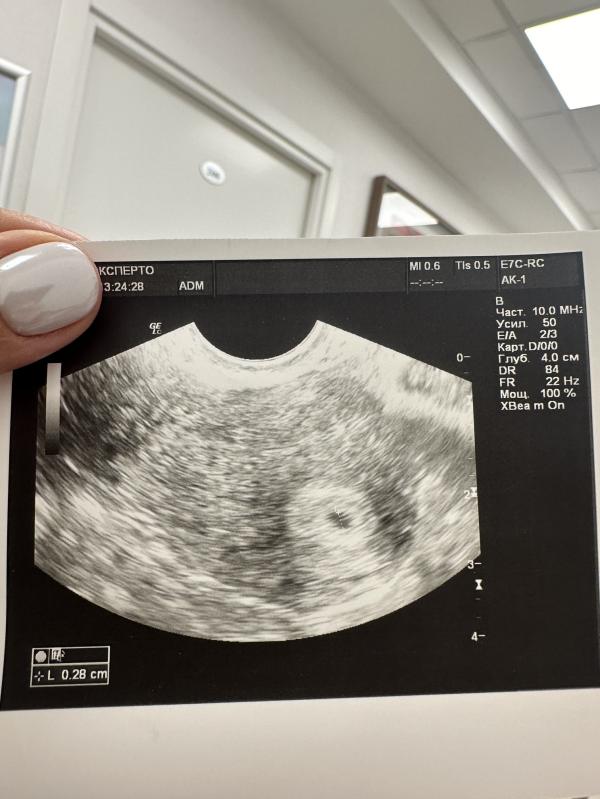

Была сегодня на узи, и сегодня мы уже увидели плодное яйцо в матке😍

Срок 5 акушерских недель и 2 дня, размер бусинки 2.8 мм✨Расти моё счастье ❤️

@yuliafilip, мне врач сказала, но на моем снимке слева внизу, также написан размер L-0.28)